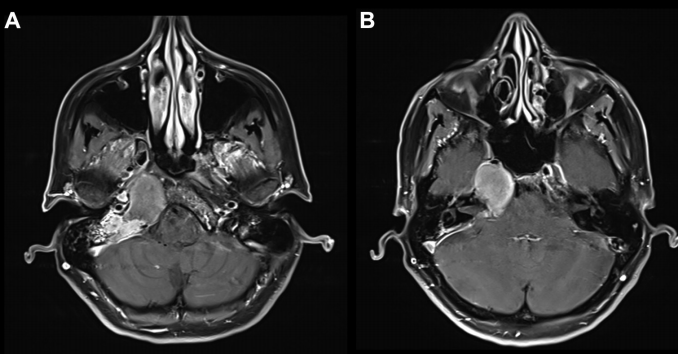

增强 MRI 显示病灶在岩尖、耳蜗和内听道侧面和后部出现均匀强化病灶, T2 低信号和 T1 高信号,病灶导致右侧内听道 ICA 和海绵窦向前移位。